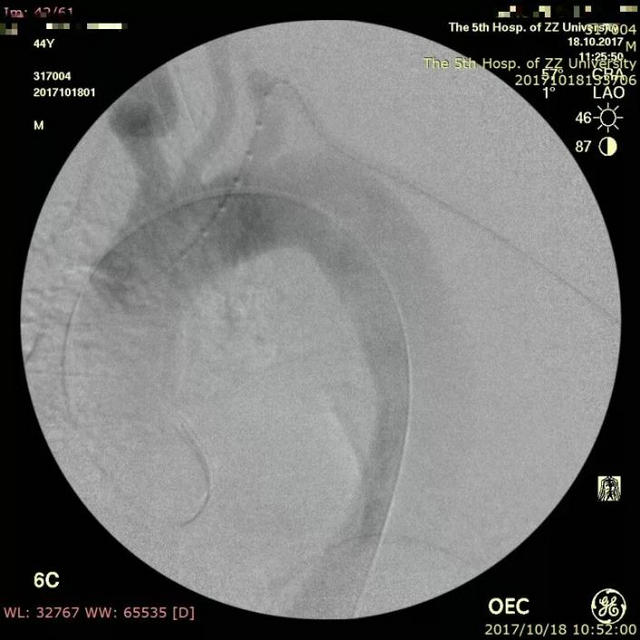

近日,郑州大学五附院血管外科就成功为一位累及左锁骨下动脉的病人开展了这项技术,取得了很好的效果。这是一位44岁的中年男性,突发腰背部疼痛,曾在当地按泌尿系结石进行体外碎石治疗,治疗后疼痛仍不缓解,再查CTA提示主动脉夹层,随即急诊转入进一步治疗。主动脉CTA显示Stanford B型夹层,但夹层累及左锁骨下动脉,如果不封堵该动脉则存在夹层继续进展的较大可能,而封堵了该动脉则可能导致头颅和左上肢的缺血症状,而且患者年轻,保留左锁骨下动脉的必要性大。经过科室的充分术前讨论,最后决定对该患者行“胸主动脉夹层覆膜支架腔内隔绝术,左锁骨下动脉原位激光开窗并支架置入术”,手术由王兵教授和崔文军副主任医师亲自操刀,手术成功,按原定计划顺利完成,用时不到2小时。术后患者恢复良好,腰背部疼痛消失,左上肢血供良好,肱动脉、桡动脉搏动有力,无头晕等不适发生,复查主动脉CTA提示支架位置、形态良好,夹层隔绝良好,左锁骨下动脉支架通畅,近期即将顺利出院。

▲ 造影显示胸主动脉夹层